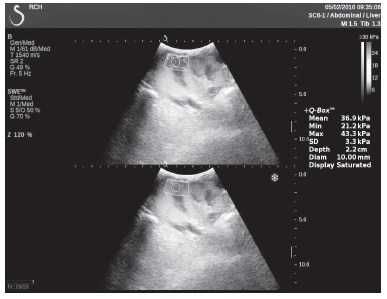

Клинический пример из первой группы. Пациент М., с хронической почечной недостаточностью. Трансплантация почки произведена от живого родственного донора. Трансплантат находится в правой подвздошной области. При нормальном функциональном состоянии трансплантата, показатели цветовой и спектральной допплерографии оценивались как удовлетворительные, с индексом резистентности не более 0,60 (рис. 1); показатели жесткости паренхимы почечного трансплантата при УЭСВ на различных участках составили от 20,05 до 29,18 кПа (рис. 2-4).

Рисунок 2. Исследование в режиме ультразвуковой эластографии сдвиговой волны у пациента М.: жесткость паренхимы в зоне медиального края трансплантата 19,8 кПа

Клинический пример из второй группы. Пациент К. перенес операцию пересадки почки от живого родственного донора. Трансплантат в левой подвздошной области. Индекс резистентности в междольковых артериях составил 0,70 (рис. 5). В сегментарных артериях индекс резистентности составил 0,66 (рис. 6). Показатели жесткости паренхимы почечного трансплантата при режиме УЭСВ составили от 31,6 до 36,9 кПа (рис. 7-9).

Рисунок 7. Исследование в режиме ультразвуковой эластографии сдвиговой волны у пациента К.: жесткость паренхимы в зоне медиального края почечного трансплантата 36,9 кПа